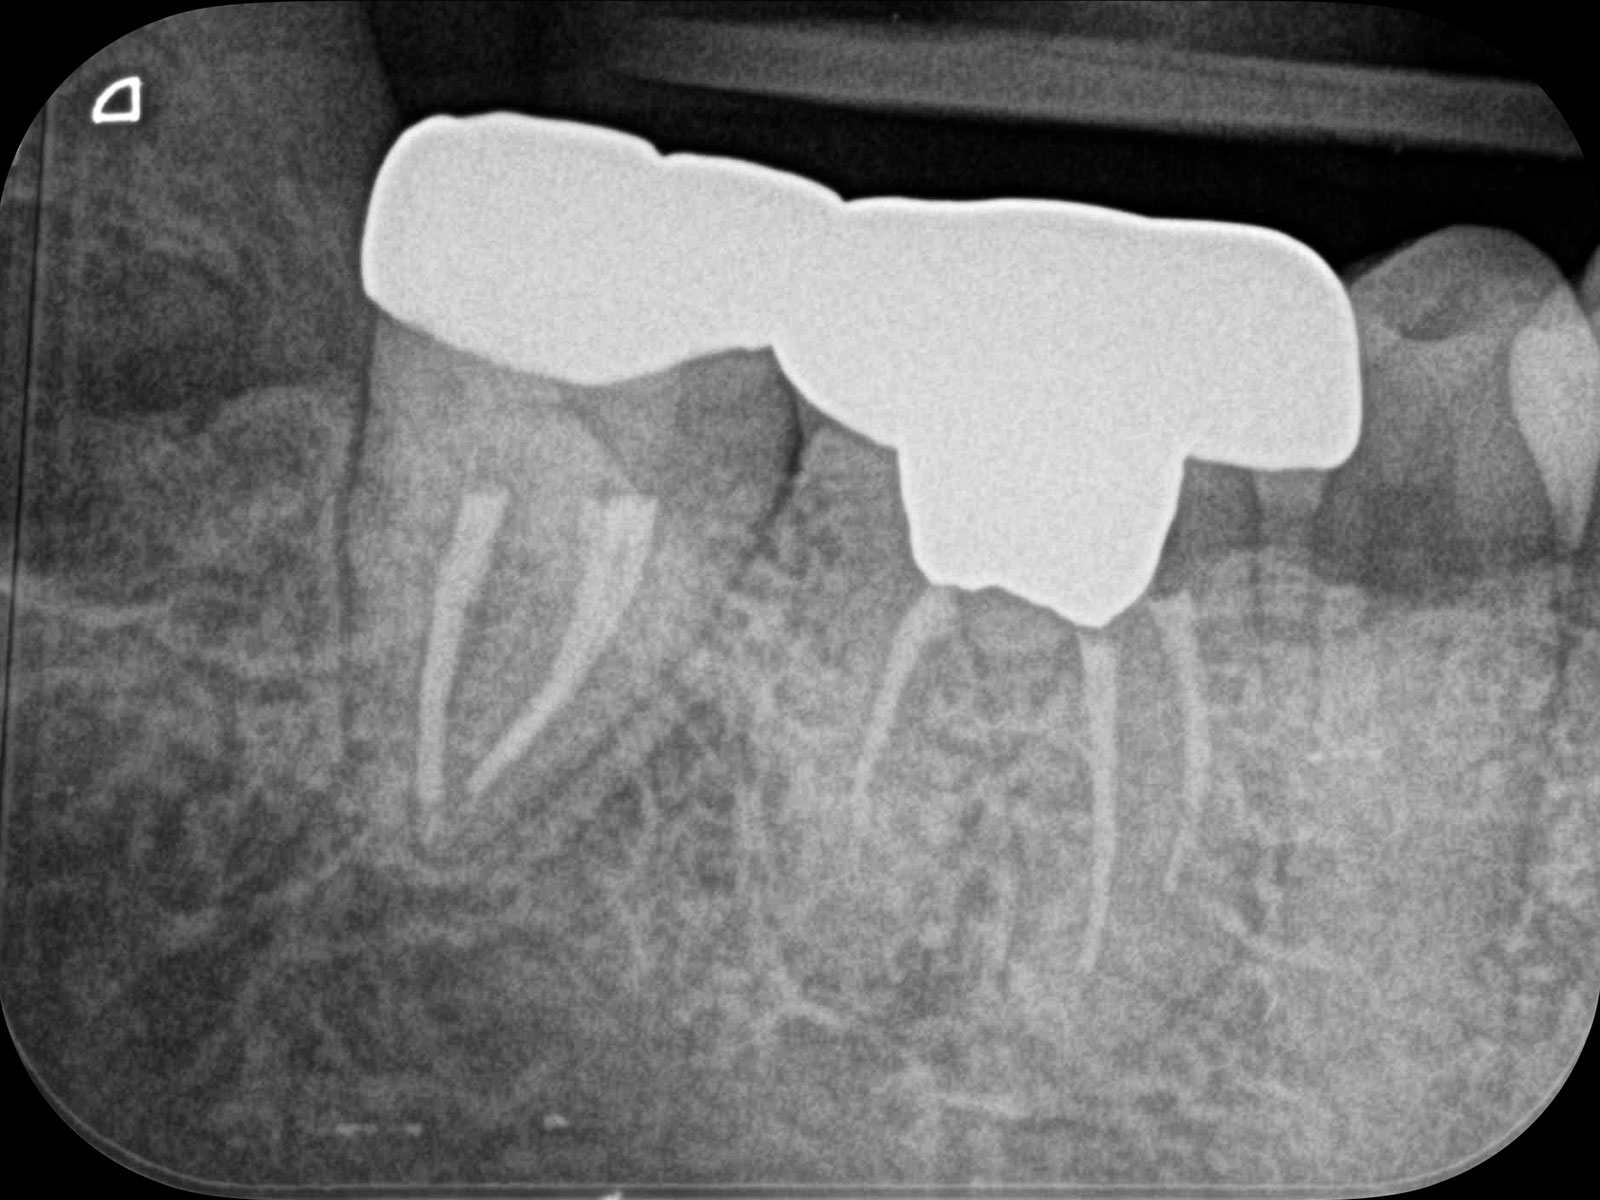

「CT」は画像診断装置の一種です。3次元的(立体的)に治療部位を撮影できるため、血管や神経の位置関係など、通常のレントゲンでは得られない情報も得ることができます。

上記の画像は、CT(左)とレントゲン(右)の比較です。丸をつけている箇所が病巣なのですが、レントゲンだと発見できないことがおわかりいただけるかと思います。